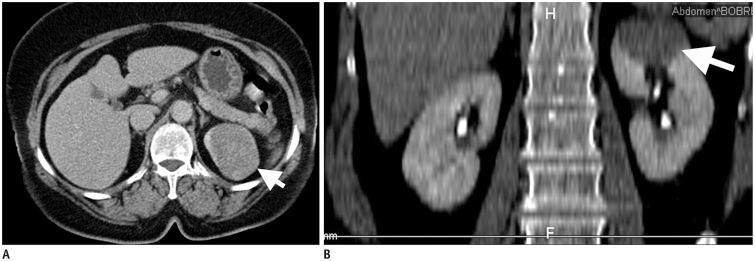

Malignant kidney neoplasms are the most frequently encountered solid kidney masses. Although renal cell carcinoma is the major renal malignancy, other solid malignant renal masses should be considered in the differential diagnosis of solid renal masses that do not contain a macroscopic fatty component. In this pictorial essay, we present the imaging findings of a primitive neuroectodermal tumor, primary liposarcoma of the kidney, primary neuroendocrine tumor, leiomyosarcoma, synovial sarcoma, malignant fibrous histiocytoma, sclerosing fibrosarcoma and renal metastasis of osteosarcoma.

恶性肾肿瘤是最常见的实性肾肿块。虽然肾细胞癌是主要的肾脏恶性肿瘤,但在鉴别诊断不包含肉眼可见脂肪成分的实性肾肿块时,应考虑其他实性恶性肾肿块。在这篇影像论文中,我们展示了原始神经外胚层肿瘤、肾原发性脂肪肉瘤、原发性神经内分泌肿瘤、平滑肌肉瘤、滑膜肉瘤、恶性纤维组织细胞瘤、硬化性纤维肉瘤以及骨肉瘤肾转移的影像学表现。